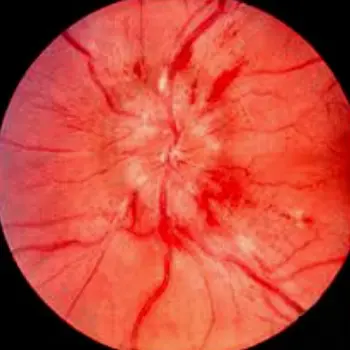

Papilledema

Increased intracranial pressure or Blood pressure

Findings